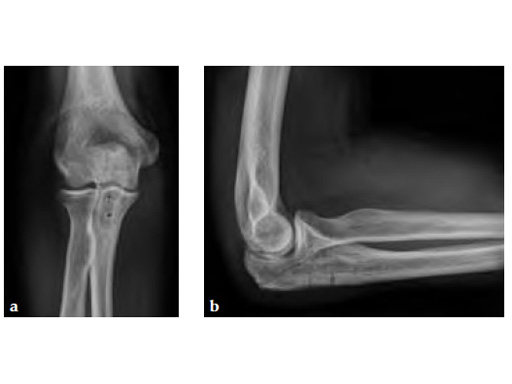

Fig 3ab X-rays 5 months postoperatively.